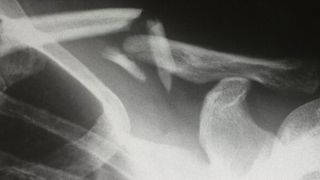

Eines der Ergebnisse der ersten Förderphase für das Miracle-Projekt: eine hochpräzise robotische Endoskospitze mit integrierter Laser-Knochensäge.(Bild:  Frank Brüderli)

Eines der Ergebnisse der ersten Förderphase für das Miracle-Projekt: eine hochpräzise robotische Endoskospitze mit integrierter Laser-Knochensäge.